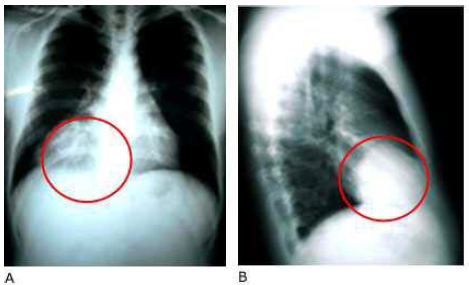

Paciente masculino, de 28 años de edad, que en un chequeo de rutina, en la radiografía de tórax, se observa imagen radiopaca paracardiaca derecha (Fig. 1).